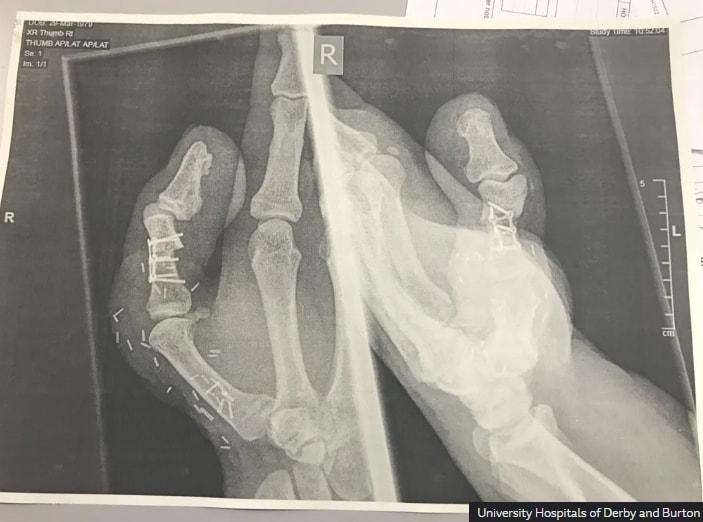

사고 직후 그는 인근 병원으로 옮겨졌고, 의료진은 여러 재건 수술 방법을 고심한 끝에 리의 오른발 엄지발가락을 절단해 잘려 나간 엄지에 붙이는 이식 수술을 진행했다.

이후 발과 손을 동시에 수술하는 복합 수술은 총 10시간가량 소요됐다. 수술은 성공적으로 끝났지만 회복 과정은 쉽지 않았다.